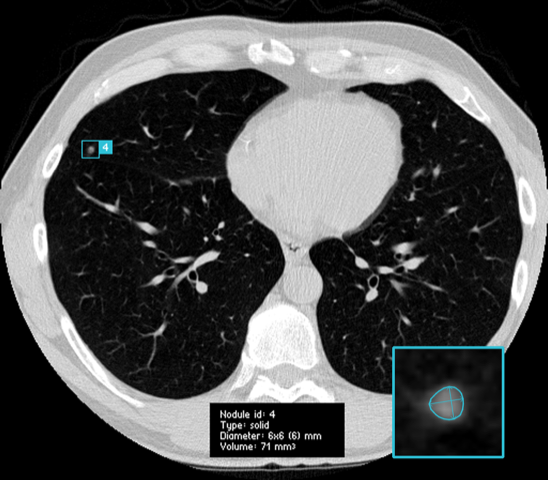

Screening of high risk groups could potentially increase early detection and thereby improve the survival rate [5; 6]. However, the (cost-) effectiveness of screening would be largely dependent on the skill, alertness and experience level of the reading radiologists, as potentially malignant lesions are easy to overlook due to the rich vascular structure of the lung (see Figure 1). A way to reduce observational oversights would be to use second readings [7; 8], a practice in which two readers independently interpret an image and combine findings, but this would also drastically add to the already increasing workload of the radiologist [9], and increase the cost of care. Thus, a potentially much more cost-effective and accurate approach would be to introduce computer aided detection (CAD) software as a second reader to assist in the detection of lung nodules [10; 11].

All scans from the NLST and LIDC/IDRI datasets with an original slice thickness equal to or less than 2.5mm were processed by the same candidate generation model to provide center coordinates of potential nodules. These center coordinates were used to extract patches from the original scans, where each voxel represents mm of lung tissue. Values of interest for nodule detection lie approximately between -1000 Hounsfield Units (air) and 300 Hounsfield Units (soft-tissue) and this range was normalized to a range.